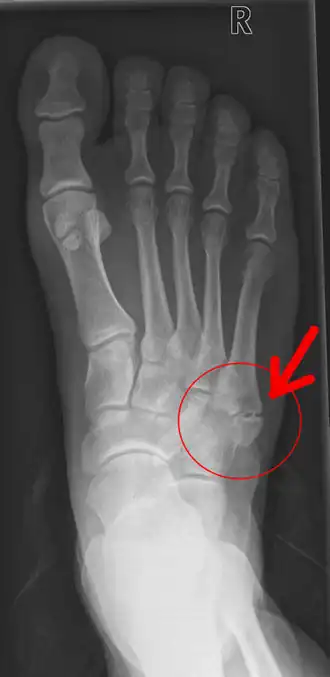

Pseudartrose aan de rechtervoet ter hoogte van het vijfde middenvoetsbeentje (basis metatarsalis V)

Pseudartrose of pseudoartrose (Grieks: ψευδή, vals, onwaar en άρθρον, gewricht) is het verschijnsel dat optreedt wanneer een botbreuk niet vastgroeit, en er een vals gewricht ontstaat. Wanneer er na zes maanden geen sprake is van consolidatie, dat wil zeggen vastgroeiing, tussen de twee of meer delen van een fractuur, is er sprake van non union en dus van pseudartrose. Als de delen over een periode langer dan vier maanden maar korter dan zes maanden niet vastgegroeid zijn, is er sprake van vertraagde botheling of delayed union.

Bij pseudartrose kan onderscheid worden gemaakt tussen een hypertrofe en een atrofe vorm. De hypertrofe vorm laat wel callusvorming rond de breuk zien, terwijl toch sprake is van non-union. Bij deze fracturen bestaat de therapie met name uit stabiliserende maatregelen. Gipsen of de bothelften middels een plaat of schroeven vastzetten zijn dan de aangewezen therapie. De atrofe vorm van pseudartrose geeft op een röntgenfoto een beeld waarbij het natuurlijke genezingsproces duidelijk achterwege blijft, er wordt dan namelijk geen callus gevormd. Bij deze vorm van pseudartrose moet neovascularisatie op de voorgrond staan. Dit kan worden bevorderd door een spongiosaplastiek uit te voeren, met donorbot of eigen bot van de patiënt uit bijvoorbeeld de bekkenkam. Ook een schroef die enige werking in het bot vertoont (en dus niet geheel vastzit), kan callusvorming bevorderen.